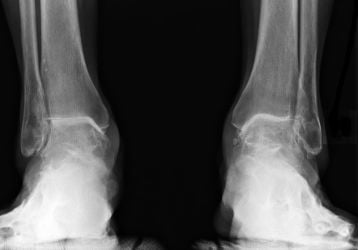

Эндопротезирование голеностопного сустава: показания, операция и реабилитация

Эндопротезирование голеностопного сустава: показания к операции, период реабилитации. Отличия от артродеза. Разновидности имплантов.